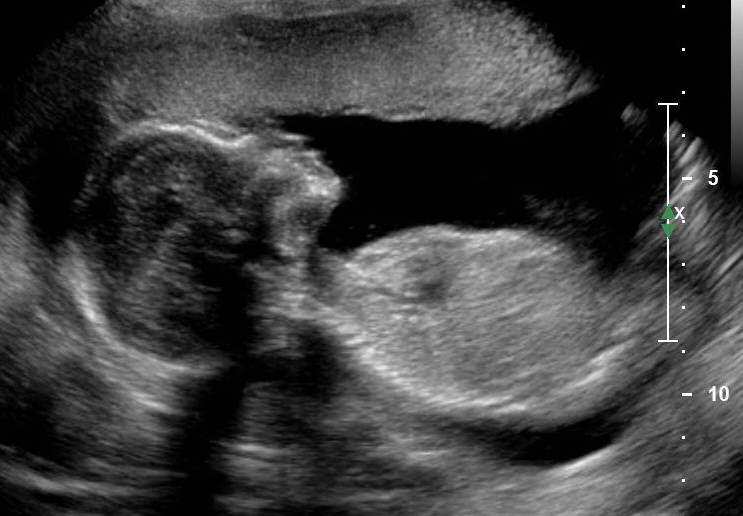

Энем узи

Энем узи 100 фотографий